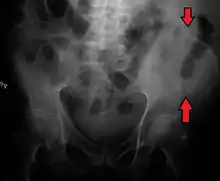

A fracture of the left iliac wing